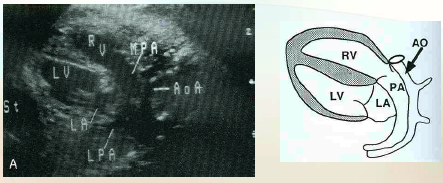

what is speciat about these veiws of the <3 ?

Right Ventricular Outflow Tract

what does the rt ventricular outflow tract (RVOT) demonstrate?

Demonstrates main pulmonary artery